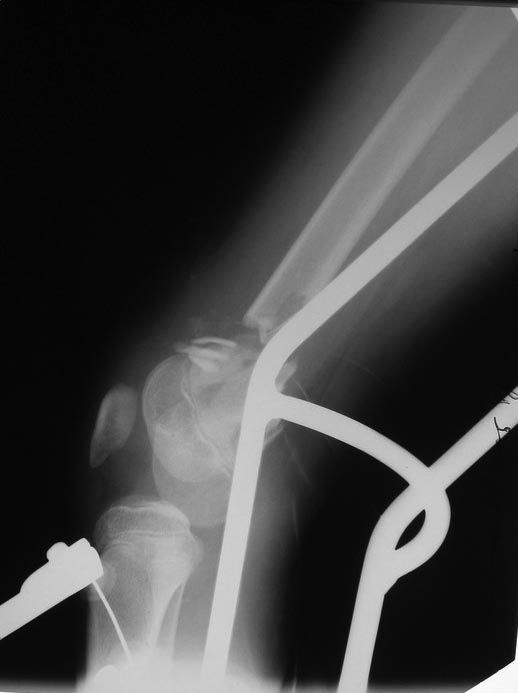

На одном бедре межмыщелковый перелом и там мыщелки немного разъехались.

Голень там тоже сломана в н/3 обе кости. Снимок голени в боковой

проекции сделан не был.